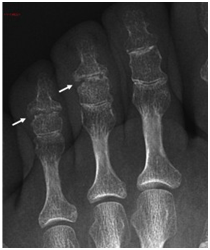

Εκτός από τα χέρια, η ΔΟΑ μπορεί να προσβάλει και τα δάκτυλα των ποδιών (Ehrlich, 1972; McKendry, 1985; Mas and Rotes-Querol, 2007; Anandarajah et al, 2009), όπως και, σπάνια, μεγάλες αρθρώσεις (Ehrlich, 1972; Keats et al, 1981).

Οι κλασικές ακτινολογικές αλλοιώσεις της ΔΟΑ παρατηρούνται στις ΑΦΦ και τις ΕΦΦ αρθρώσεις. Εχουν επίσης περιγραφεί στα πόδια, γόνατα, ισχία, ώμους και ΣΣ (Belhorn and Hess, 1993; Keats, 1981; Swezey and Alexander, 1971; Utsinger et al, 1978).

ΕΙΚΟΝΑ 1c. Διαβρώσεις των φαλαγγοφαλαγγικών αρθρώσεων των ποδιών σε ασθενή με ΔΟΑ των χεριών και των ποδιών